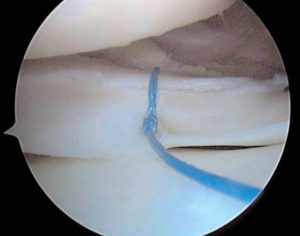

Σε περιφερικές ρήξεις που υπάρχει σχετική αιμάτωση και αγγείωση στον μηνίσκο κυρίως σε νέα άτομα κάτω των 35-40 ετών γίνεται προσπάθεια συρραφής του μηνίσκου.

Επίσης σε αποσπαστικη ρήξη ρίζας οπισθίου κέρατος μηνίσκου ( meniscal root tear) σε σχετικά νέα άτομα γίνεται αρθροσκοπική συρραφή και σταθεροποίηση.

Στις πλείστες όμως περιπτώσεις που η ρήξη του μηνίσκου είναι κεντρικότερα, στις περιοχές αυτές η αιμάτωση είναι ελλιπής και τότε αντιμετωπίζεται με μερική μηνισκεκτομή δηλαδή αφαιρείται τμήμα του ρηθέντος μηνίσκου με προσπάθεια να διατηρηθεί το μεγαλύτερο μέρος του μηνίσκου ακέραιο.

Η επέμβαση διαρκεί αναλόγως της πάθησης από 40 λεπτά (για μερική μηνισκεκτομή) μέχρι 90 λεπτά ( για συρραφή μηνίσκου).